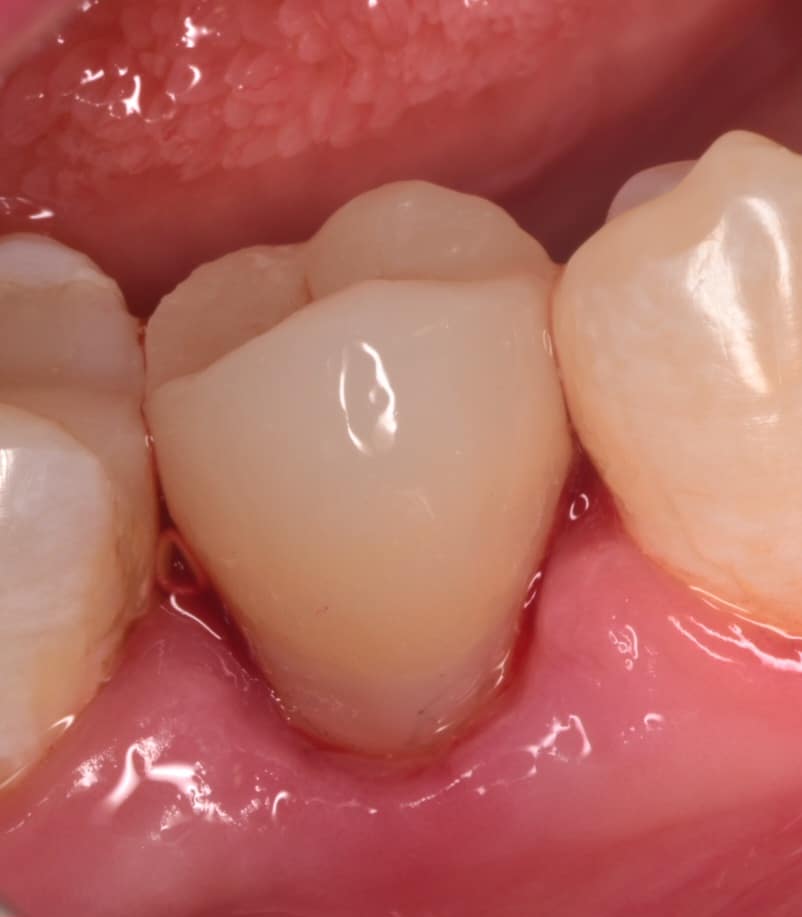

Immediate result after rubberdam removal

2 weeks later , healing as it should be